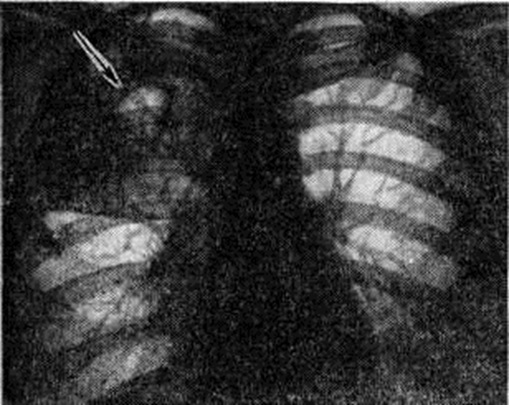

Рис. 2.

Рентгенограмма грудной клетки при первичном туберкулёзном комплексе (прямая проекция): 1 — участок уплотнения лёгочной ткани (очаг первичной пневмонии); 2 — инфильтрация периваскулярной и перибронхиальной ткани между очагом в лёгком и корнем лёгкого (дорожка); 3 — расширенный и уплотнённый корень правого лёгкого.